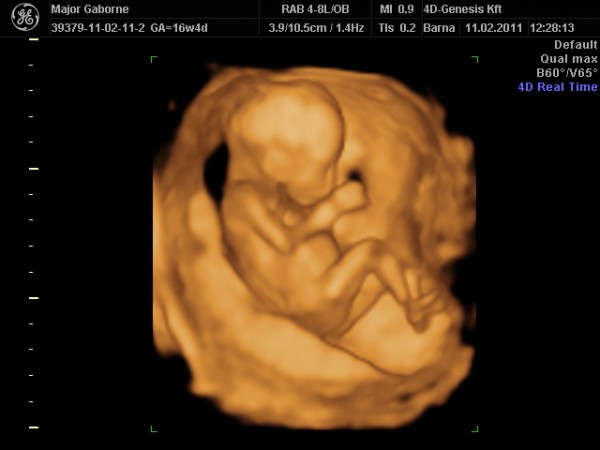

A 13. héten elmentünk uh-ra, ahol magabiztosan lefeküdtem az ágyra, tudtam, nem látunk majd kukit. Kitaláltátok, ugye? Az első másodpercben szétterpesztett, hatalmas fütyit mutatott. Nem volt kérdés…